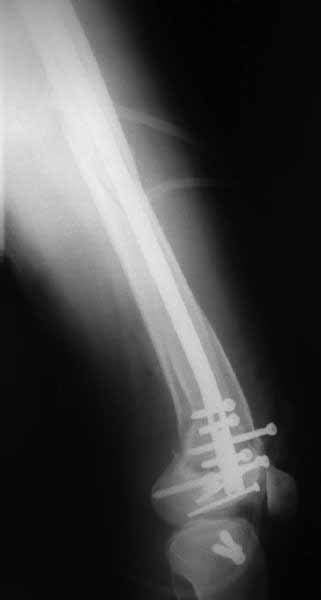

У больных как в этом случае, с вовлечением двух мыщелков правильно, что сделали вытяжение до операции. Здесь имеется флексионный компонент на другой стороне, и я бы рекомендовал операцию делать из двух доступов. Сперва фиксировать медиальную колонну custom made пластиной, обычно 1/3 тубулярной пластиной в 4.5 мм, потому что пока производители опаздывают с медиальной пластиной.

Пластину надо устанавливать на апексе перелома, иначе фрагмент начнет сползать. А на второй стороне, если имеется большой одиночный фрагмент тогда проблем не бывает, и их можно собрать компрессирующими винтами. Проблема наступает тогда когда многофрагментраность на латеральной стороне, где надо применить комбинированный метод, иногда несколькими пластинами. Или сменой позиции установки пластины, чтобы максимально прикрыть перелом и создать боковую поддержку.

Здесь пример медиальной пластины и латеральный комбинированный метод (у второго больного старый перелом тибиал плато, леченный где то и когда то)